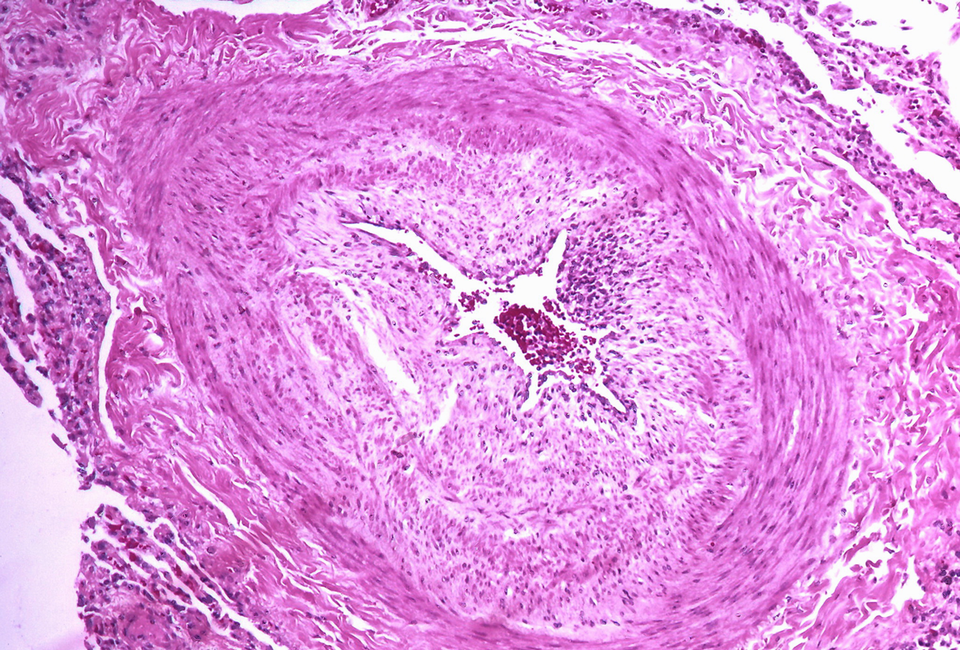

Die innere Membran des Lungenstroms hat sich verdichtet – eine Belastung für das rechte Herz. Die innere Membran des Lungenstroms hat sich verdichtet – eine Belastung für das rechte Herz. © Flickr/Yale Rosen (CC BY-SA 2.0)